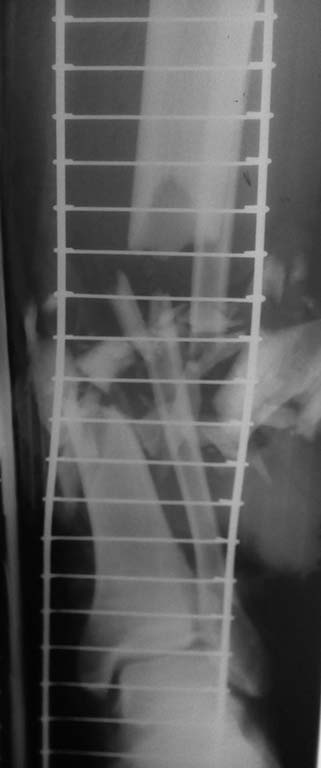

Поступил пациент с открытым (тип IIIВ по Gustillo-Andersen) переломом

костей голени.

Травма на производстве 17.05.16 на ногу упал тяжелый кусок кирпичной

стены. При поступлении на уровне приемного покоя обследован клинически и

рентгенологически, осмотрен дежурным реаниматологом, начата инфузионная

терапия. Сразу после поступления условиях перевязочной приемного покоя

дежурным травматологом произведена первичная хирургическая обработка

раны, наложены ас.повязки, наложена система скелетного вытяжения с

грузом 4 кг по оси голени.

Выполнено острое укорочение малоберцовой и большеберцовой костей с

опилом торцов основных отломков и последующим укрытием области

перелома мышечными пластами. Наложен стержневой аппарат наружной

фиксации (три стержня Штеймана установлены в прокисмальный отломок и три

в дистальный отломок). С целью дренирования установлены полутрубчатые

выпускники. Ушивание кожи без натяжения. После

выполнения операции произведена оценка сосудистого статуса дистальной

части правой голени и правой стопы. Капиллярная реакция сохранена (2

сек), пульсация на задней большеберцовой артерии определяется. Пульсация

на тыльной артерии стопы не определяется. В послеоперационном периоде

Ds: Открытый многооскольчатый перелом (тип IIIВ по

Gustillo-Andersen) нижней трети диафизов обеих костей правой голени со

смещением отломков, дефектом костного вещества, дефектом мягких тканей,

повреждением переднего сосудисто-нервного пучка правой голени,

повреждением ветвей малоберцового нерва на уровне средней-нижней трети

правой голени. На данный момент остается зона колликвационного некроза

на границе нижней средней трети голени (фото). Кость пока в ране не

выступает.